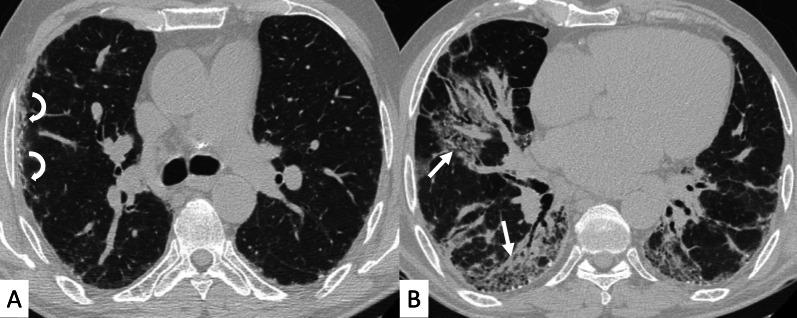

Connective tissue diseases (CTDs) include a spectrum of disorders that affect the connective tissue of the human body; they include autoimmune disorders characterized by immune-mediated chronic inflammation and the development of fibrosis. Lung involvement can be misdiagnosed, since pulmonary alterations preceded osteo-articular manifestations only in 20% of cases and they have no clear clinical findings in the early phases. All pulmonary structures may be interested: pulmonary interstitium, airways, pleura and respiratory muscles. Among these autoimmune disorders, rheumatoid arthritis (RA) is characterized by usual interstitial pneumonia (UIP), pulmonary nodules and airway disease with air-trapping, whereas non-specific interstitial pneumonia (NSIP), pulmonary hypertension and esophageal dilatation are frequently revealed in systemic sclerosis (SSc). NSIP and organizing pneumonia (OP) may be found in patients having polymyositis (PM) and dermatomyositis (DM); in some cases, perilobular consolidations and reverse halo-sign areas may be observed. Systemic lupus erythematosus (SLE) is characterized by serositis, acute lupus pneumonitis and alveolar hemorrhage. In the Sjögren syndrome (SS), the most frequent pattern encountered on HRCT images is represented by NSIP; UIP and lymphocytic interstitial pneumonia (LIP) are reported with a lower frequency. Finally, fibrotic NSIP may be the interstitial disease observed in patients having mixed connective tissue diseases (MCTD). This pictorial review therefore aims to provide clinical features and imaging findings associated with autoimmune CTDs, in order to help radiologists, pneumologists and rheumatologists in their diagnoses and management.

结缔组织病(CTDs)包括一系列影响人体结缔组织的疾病;它们包括以免疫介导的慢性炎症和纤维化发展为特征的自身免疫性疾病。肺部受累可能会被误诊,因为肺部改变仅在20%的病例中先于骨关节炎表现出现,且在早期阶段没有明确的临床发现。所有肺部结构都可能受累:肺间质、气道、胸膜和呼吸肌。在这些自身免疫性疾病中,类风湿关节炎(RA)的特征是普通型间质性肺炎(UIP)、肺结节和伴有空气潴留的气道疾病,而系统性硬化症(SSc)常表现为非特异性间质性肺炎(NSIP)、肺动脉高压和食管扩张。NSIP和机化性肺炎(OP)可见于多发性肌炎(PM)和皮肌炎(DM)患者;在某些情况下,可观察到小叶周围实变和反晕征区域。系统性红斑狼疮(SLE)的特征是浆膜炎、急性狼疮性肺炎和肺泡出血。在干燥综合征(SS)中,HRCT图像上最常见的表现是NSIP;UIP和淋巴细胞间质性肺炎(LIP)的报道频率较低。最后,纤维化NSIP可能是混合性结缔组织病(MCTD)患者中观察到的间质性疾病。因此,本图像综述旨在提供与自身免疫性CTDs相关的临床特征和影像学表现,以帮助放射科医生、呼吸科医生和风湿病科医生进行诊断和管理。